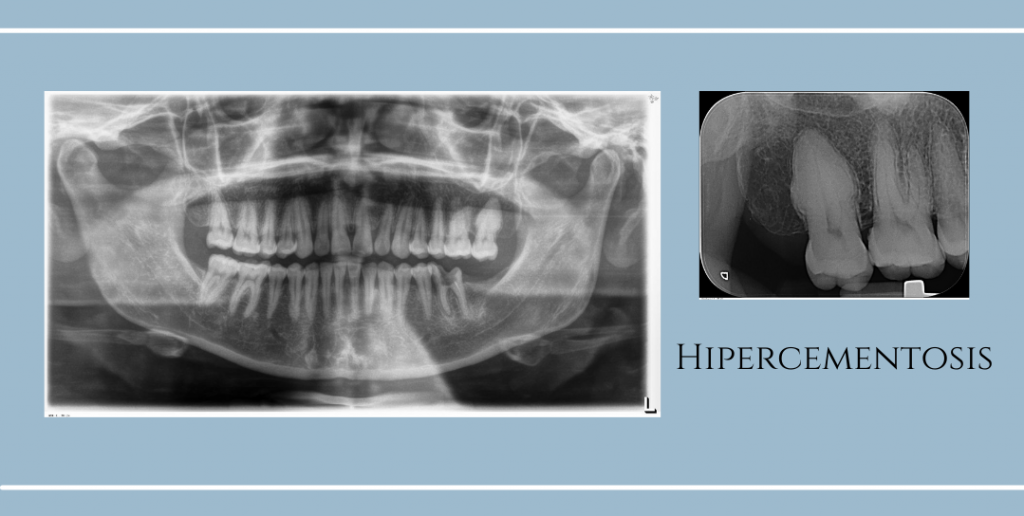

Se observa aumento en el grosor radicular en el órgano dentario 27, lo cual es compatible con Hipercementosis. En el órgano dentario 36 se observa con tratamiento parcial de endodoncia, engrosamiento del espacio del ligamento periodontal en la raíz mesial.

La hipercementosis es una condición que afecta la forma y superficie de las raíces de un órgano dentario. Se caracteriza por la acumulación excesiva de material llamado cemento radicular sobre la raíz de órgano dentario, lo que da como resultado la forma anormal. Es asintomático. Se desconoce la causa exacta, se puede presentar en personas que padecen problemas de salud como artritis, fiebre reumática, acromegalia o enfermedad de Paget o con deficiencia de la vitamina A. Por lo general se presenta en pacientes de edad avanzada.